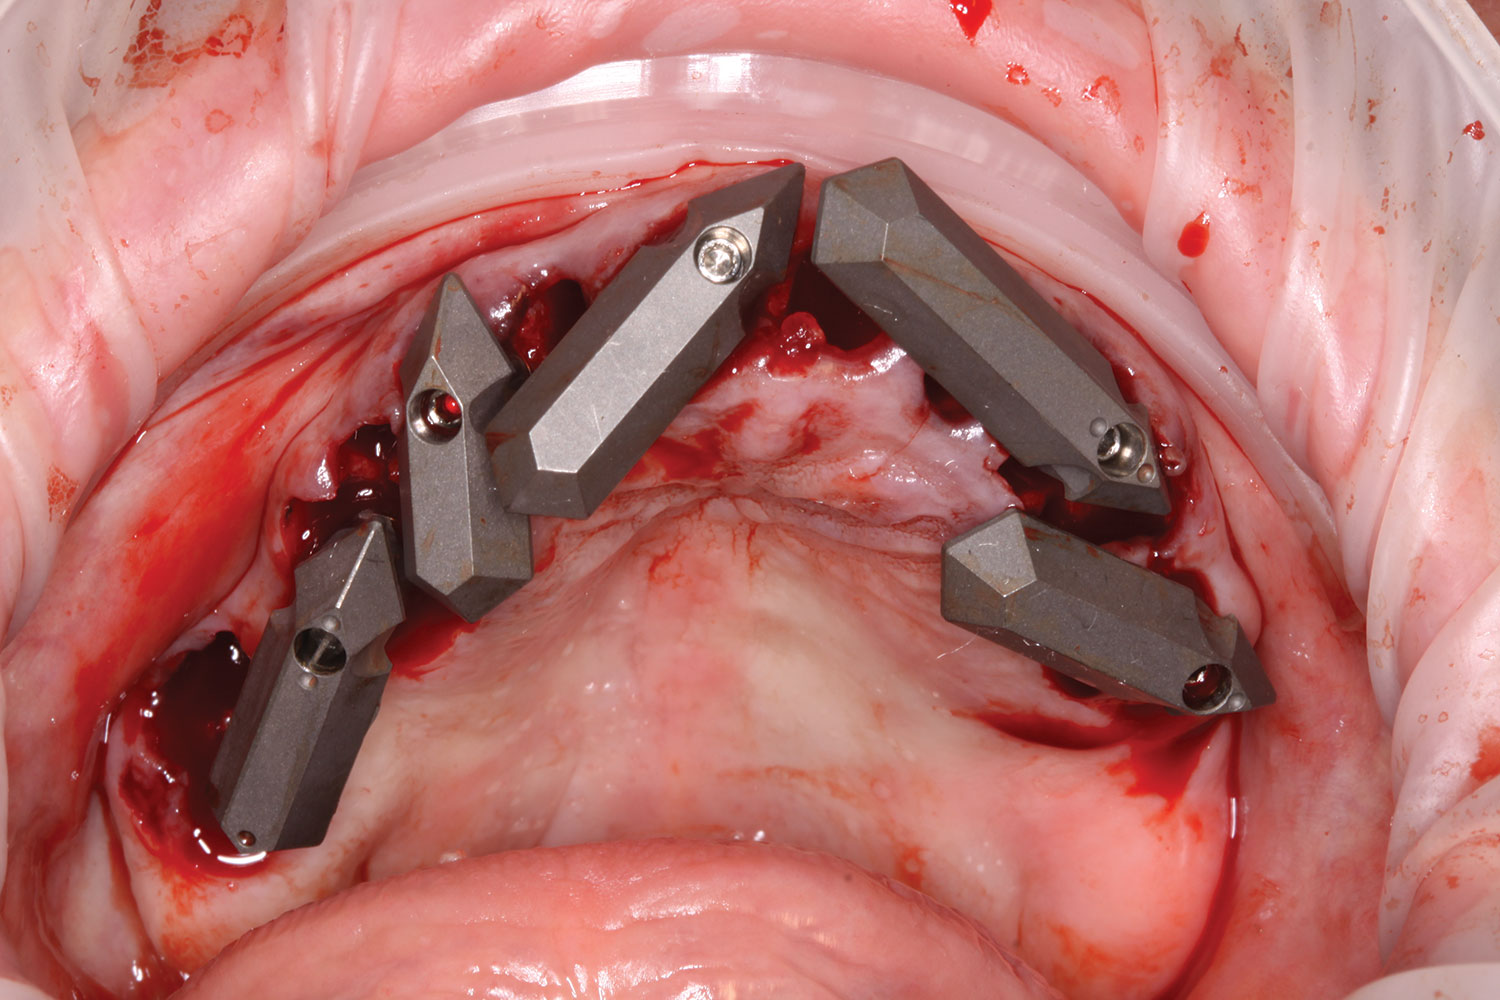

Fig 14. All implants, multi-unit abutments, and scan gauges in place.

Figure 14

Fig 15. Completion of maxillary flapless immediate implant surgery and placement of multi-unit abutments.

Figure 15